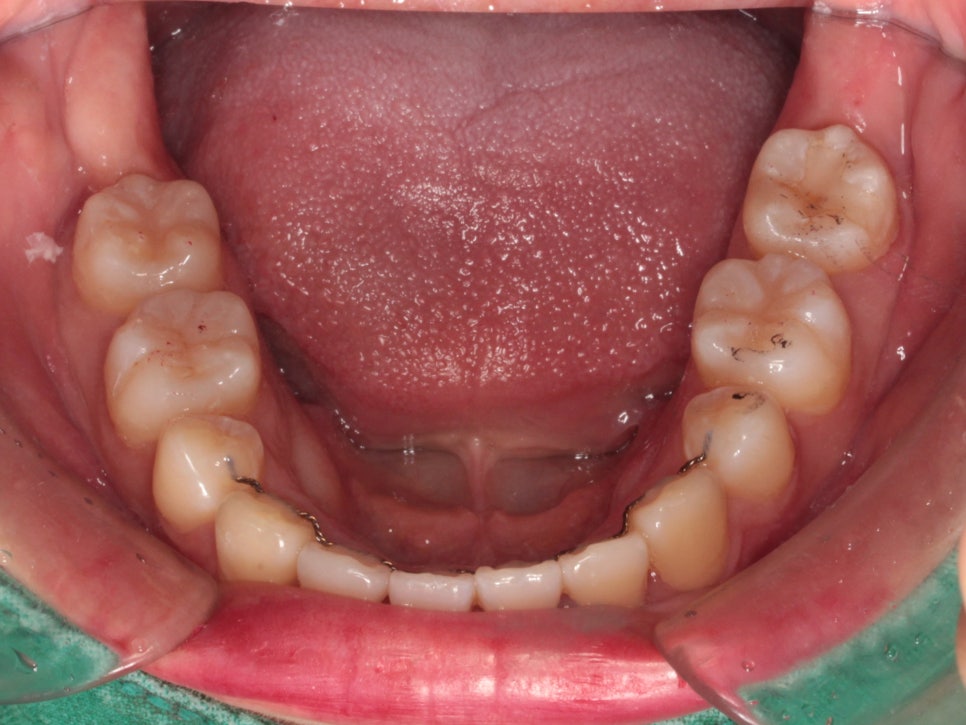

치료방법은 발치를 동반한 미니스크류 교정치료입니다.

총 6개의 미니스크류를 식립하고 치료를 했습니다

미니스크류를 잘 이용하면 얼굴이 짧아지면서 자연스러운 입술을 만들 수 있습니다.

치료기간이 조금 더 긴편이지만, 극적인 안모변화를 얻는 경우가 많습니다